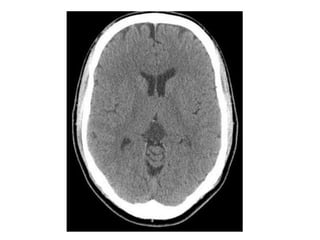

-CT :

-Typical CT finding is homogenous expansion of

tectal plate, isodense to grey matter with

minimal enhancement in postcontrast image

CT shows non-communicating hydrocephalus , note the low density lesion of

the tectal plate